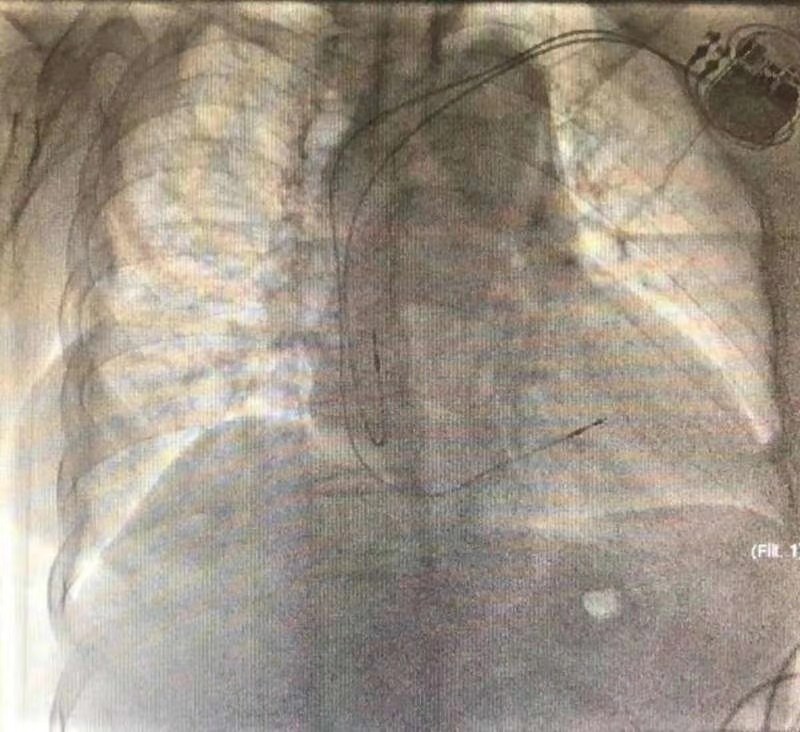

手术过程十分顺利,仅用时50分钟。术后患者表示感觉良好,无任何不适。囊袋制作细致再加上起搏器本身体积小(10cc),术后外观难以察觉起搏器的存在,不但减少了囊袋的磨损的可能还保持了美观的效果。

对于65岁以上的起搏器植入适应证患者,若患者有脑卒中高危因素(高血压、糖尿病等)或有骨关节炎、脊柱相关疾病史以及相关肿瘤高危因素者,应考虑到患者在植入起搏器之后存在需接受MRI扫描的可能,推荐此类患者植入可兼容核磁共振检查的心脏起搏器。但是,既往的抗核磁起搏器仅能兼容1.5T场强核磁共振,部分检查受到限制;同时,起搏器寿命不够长,植入后仍存在多次更换可能性;而长寿命起搏器又不能兼容核磁共振检查。Endurity MRI PM2172抗核磁长寿命小体积双腔起搏器的引入完美解决了这部分患者的需求。该起搏器已获得CE认证和国内认证,可接受在3.0T磁场强度下的全身核磁扫描;同时,起搏器体积非常小,仅为10cc,厚度仅为6mm,已达到现今工业水平的极限,但寿命并不受影响,预估仍然可以达到13年;除此之外,该设备还具有长时间记录腔内图以及做出心衰预警等先进功能。张萍教授认为新型起搏器的引入会给患者带来持久获益。